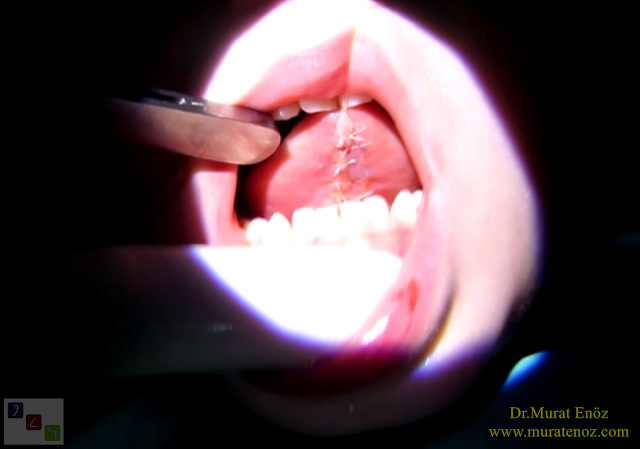

Here, the removal of the tongue tie tissue with using thermal welding device is showing. A curtain-shaped structure under the tongue is removed and it is aimed to decrease the possibility of lining of the wound edges.

• The incision line is sutured with thin absorbale stitch materials